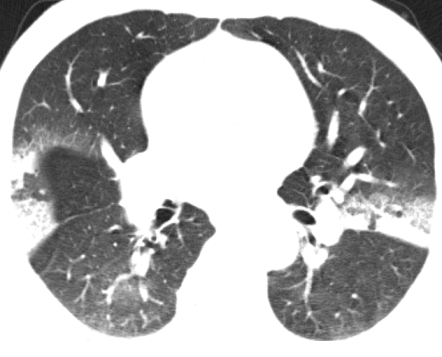

经过精心治疗,王某的症状完全消失。一个月后复查胸部 CT,结果显示较前明显吸收,这标志着王某的病情得到了有效控制,向着康复迈出了坚实的一步。信丰县中医院肺病科专家团队以卓越的医疗水平和高度的责任心,再次为患者带来了健康和希望,也赢得了广大患者的信任和赞誉。

治疗后CT影像▲